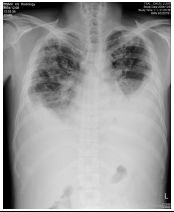

10. CC: 咳嗽 1 周,有痰